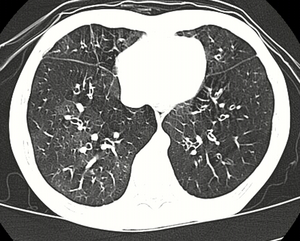

Medical imaging

Early in the disease chest radiography is typically normal but may show hyperinflation.[6] As the disease progresses a reticular pattern with thickening of airway walls may be present.[4][6] HRCT can also show air trapping when the person being scanned breathes out completely; it can also show thickening in the airway and haziness in the lungs.[11] A common finding on HRCT is patchy areas of decreased lung density, signifying reduced vascular caliber and air trapping.[6] This pattern is often described as a "mosaic pattern", and may indicate obliterative bronchiolitis.[6]